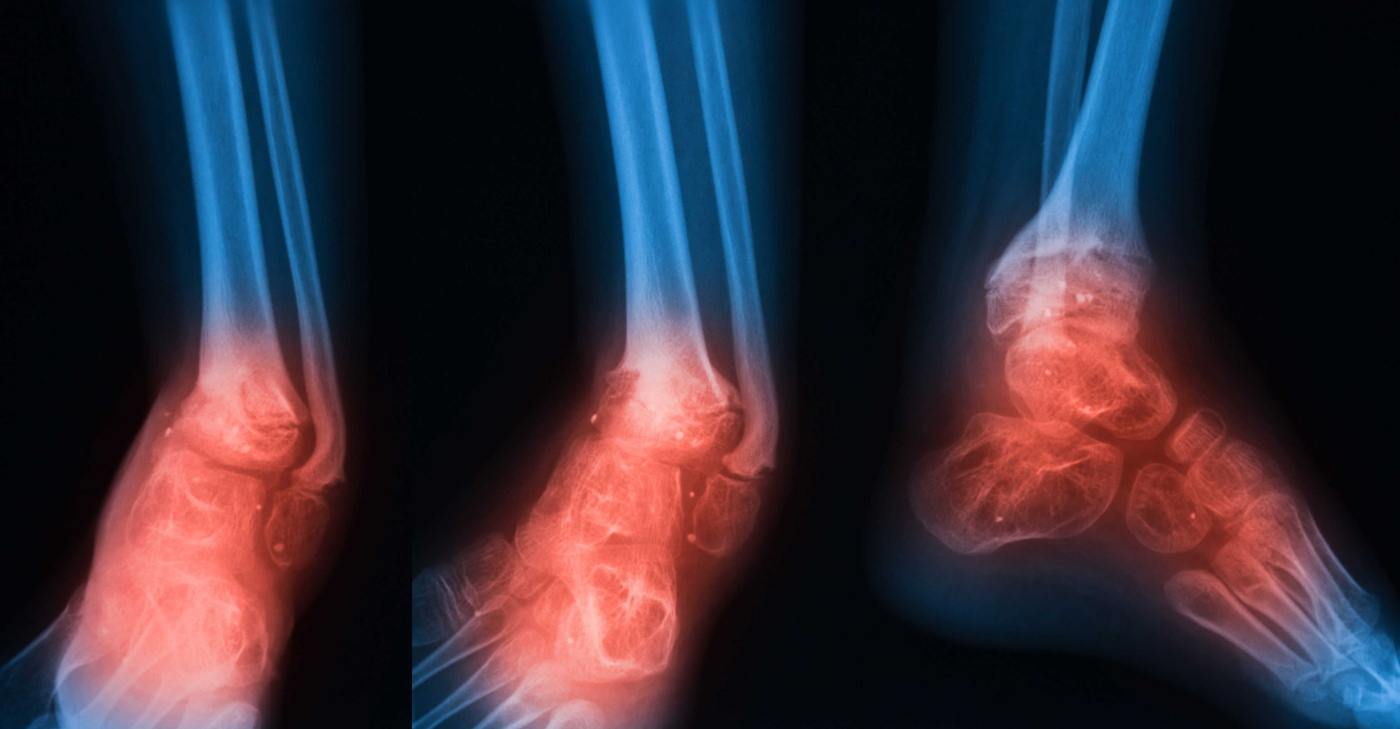

Osteomielitis adalah jangkitan tulang yang jarang berlaku tetapi serius. Jangkitan tulang boleh menjadi akut atau kronik. Jika pesakit tidak mempunyai rawatan yang betul, tulang tertentu boleh rosak secara kekal. Ia disebabkan oleh bakteria atau kulat yang menyerang tulang. Pada kanak-kanak, tempat yang paling popular di mana jangkitan tulang berlaku adalah pada tulang panjang lengan dan kaki. Sebaliknya, jangkitan kelihatan pada pinggul, tulang belakang, dan kaki.

- Kemerahan di kawasan yang dijangkiti

- Bengkak di kawasan yang terjejas